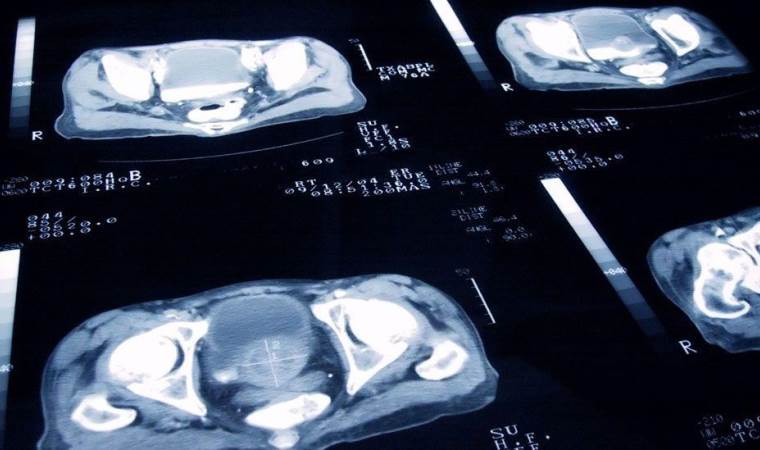

Dünyada olduğu gibi Türkiye'de de kanser vakaları yükselişini sürdürürken en hızlı artış yaşanan kanser türünün akciğer kanseri, en çok görülenin ise erkeklerde prostat kadınlarda ise meme kanseri olduğu açıklandı.

Akciğer Kanserinin en önemli nedeninin sigara olduğunu ifade eden Uzm. Dr. Gülhan Koşucu, “Akciğer Kanseri hızla artan ve erkeklerde prostat, kadınlarda meme kanserinden sonra en sık görülen ikinci kanser türüdür. Akciğer kanserinin en önemli nedeni sigaradır” dedi.

Akciğer Kanserinde tedavi belirlemesinde en önemli faktörün, kanserin tipi ve evresi olduğunu vurgulayan Koşucu, sözlerini şöyle tamamladı; “Akciğer kanseri, görüntüleme yöntemleri ile tespit edildikten sonra kesin tanı biyopsi sonrasında konur. Tedavi belirlemesinde en önemli faktör kanser tipi ve evresidir. Uygun hastalarda cerrahi yöntemle kanserin bulunduğu akciğer veya akciğer bölümü çıkartılabilir. Cerrahi işleme elverişli olmayan hastalara ise kemoterapi ve/veya radyoterapi uygulanabilmektedir. Akciğer kanserinden korunmak için risk faktörlerinden mümkün olduğunca uzak durmak, sağlıklı yaşam alışkanlıkları geliştirmek gerekmektedir.”